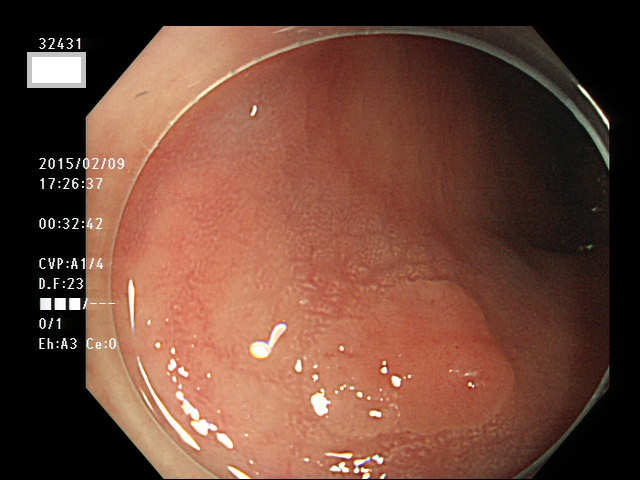

上記100名より抽出した平坦・陥凹型腺腫(=癌化の危険が高いが見落としやすい病変)の内視鏡写真